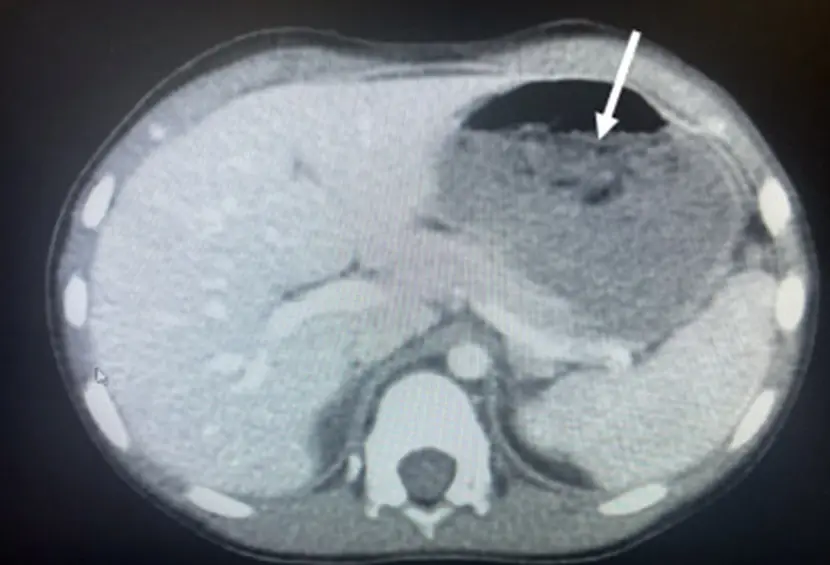

Η ομάδα των γιατρών, με επικεφαλής τον Dr. Chizite Iheonunekwu της Cleveland Clinic, ανακάλυψε το περιεχόμενο στην κοιλιά του με ακτονογραφίες, οι οποίες αποκάλυψαν τη μεγάλη μάζα.

Οι γιατροί αφαίρεσαν την τσίχλα με άκαμπτη οισοφαγοσκόπηση, με τη βοήθεια ενός μεταλλικού σωλήνα και χρησιμοποιώντας λαβίδες για να πιάσουν τη μάζα.